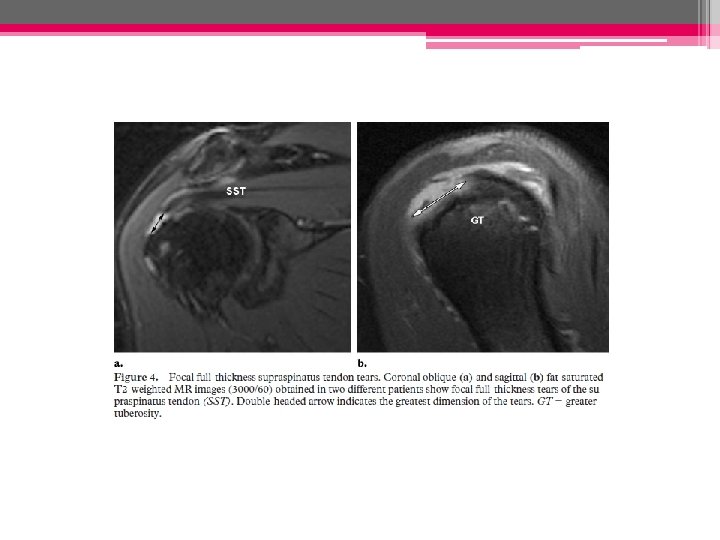

• Rupture transfixiante: - intéresse de manière focale toute l’épaisseur du tendon ( « trou » traversant le tendon) crée une communication +/- large entre la BSAD et la cavité articulaire gléno-humérale • Rupture complète (ou totale) Interrompt la totalité des fibres du tendon et s’accompagne volontiers d’une rétraction du moignon tendineux (écartement des deux extrémités tendineuses)

Taille de la rupture • Doit être précisée dans le grand axe du tendon et le plan perpendiculaire • On distingue: - les petites ruptures < 2 cm - les ruptures larges 2 -4 cm - les ruptures massives >4 cm

IRM: - Hypersignal tendineux modéré en DP, intense (de type liquidien) en pondération T 2 - Dégénerescence graisseuse et amyotrophie: pondération T 1 - NB: pfs réaction oedémateuse de la MO adjacente au tendon # pathologie tumorale, septique ou rhumatismale

- Tendon sus-épineux: coupes frontales obliques++ - Tendon ss-épineux: coupes transversales - Coupes sagittales obliques: apprécier l’extension ant-post de la rupture